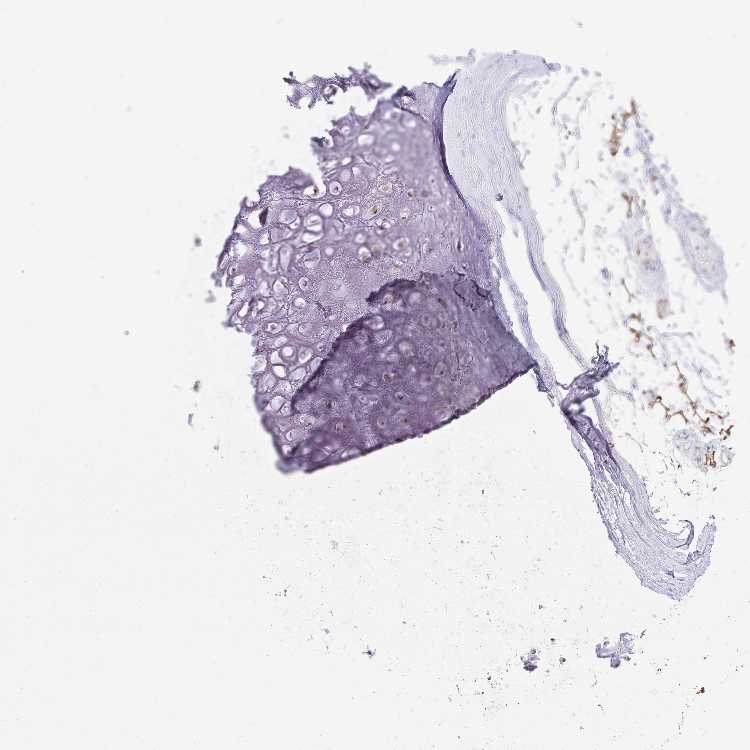

SOFT TISSUE 1 - Antibody stainingi

Antibody staining in the annotated cell types in the current human tissue is reported as not detected, low, medium, or high, based on conventional immunohistochemistry profiling in selected tissues. This score is based on the combination of the staining intensity and fraction of stained cells.

Each image is clickable and will lead to virtual microscopy that enables deeper exploration of all samples and also displays staining intensity scores, fraction scores and subcellular localization as well as patient and tissue information for each sample.

Antibody HPA047814Antibody HPA060902Antibody CAB009562

Chondrocytes -Not detectedLow

Fibroblasts Not detectedNot detectedHigh

Peripheral nerve --Not detected